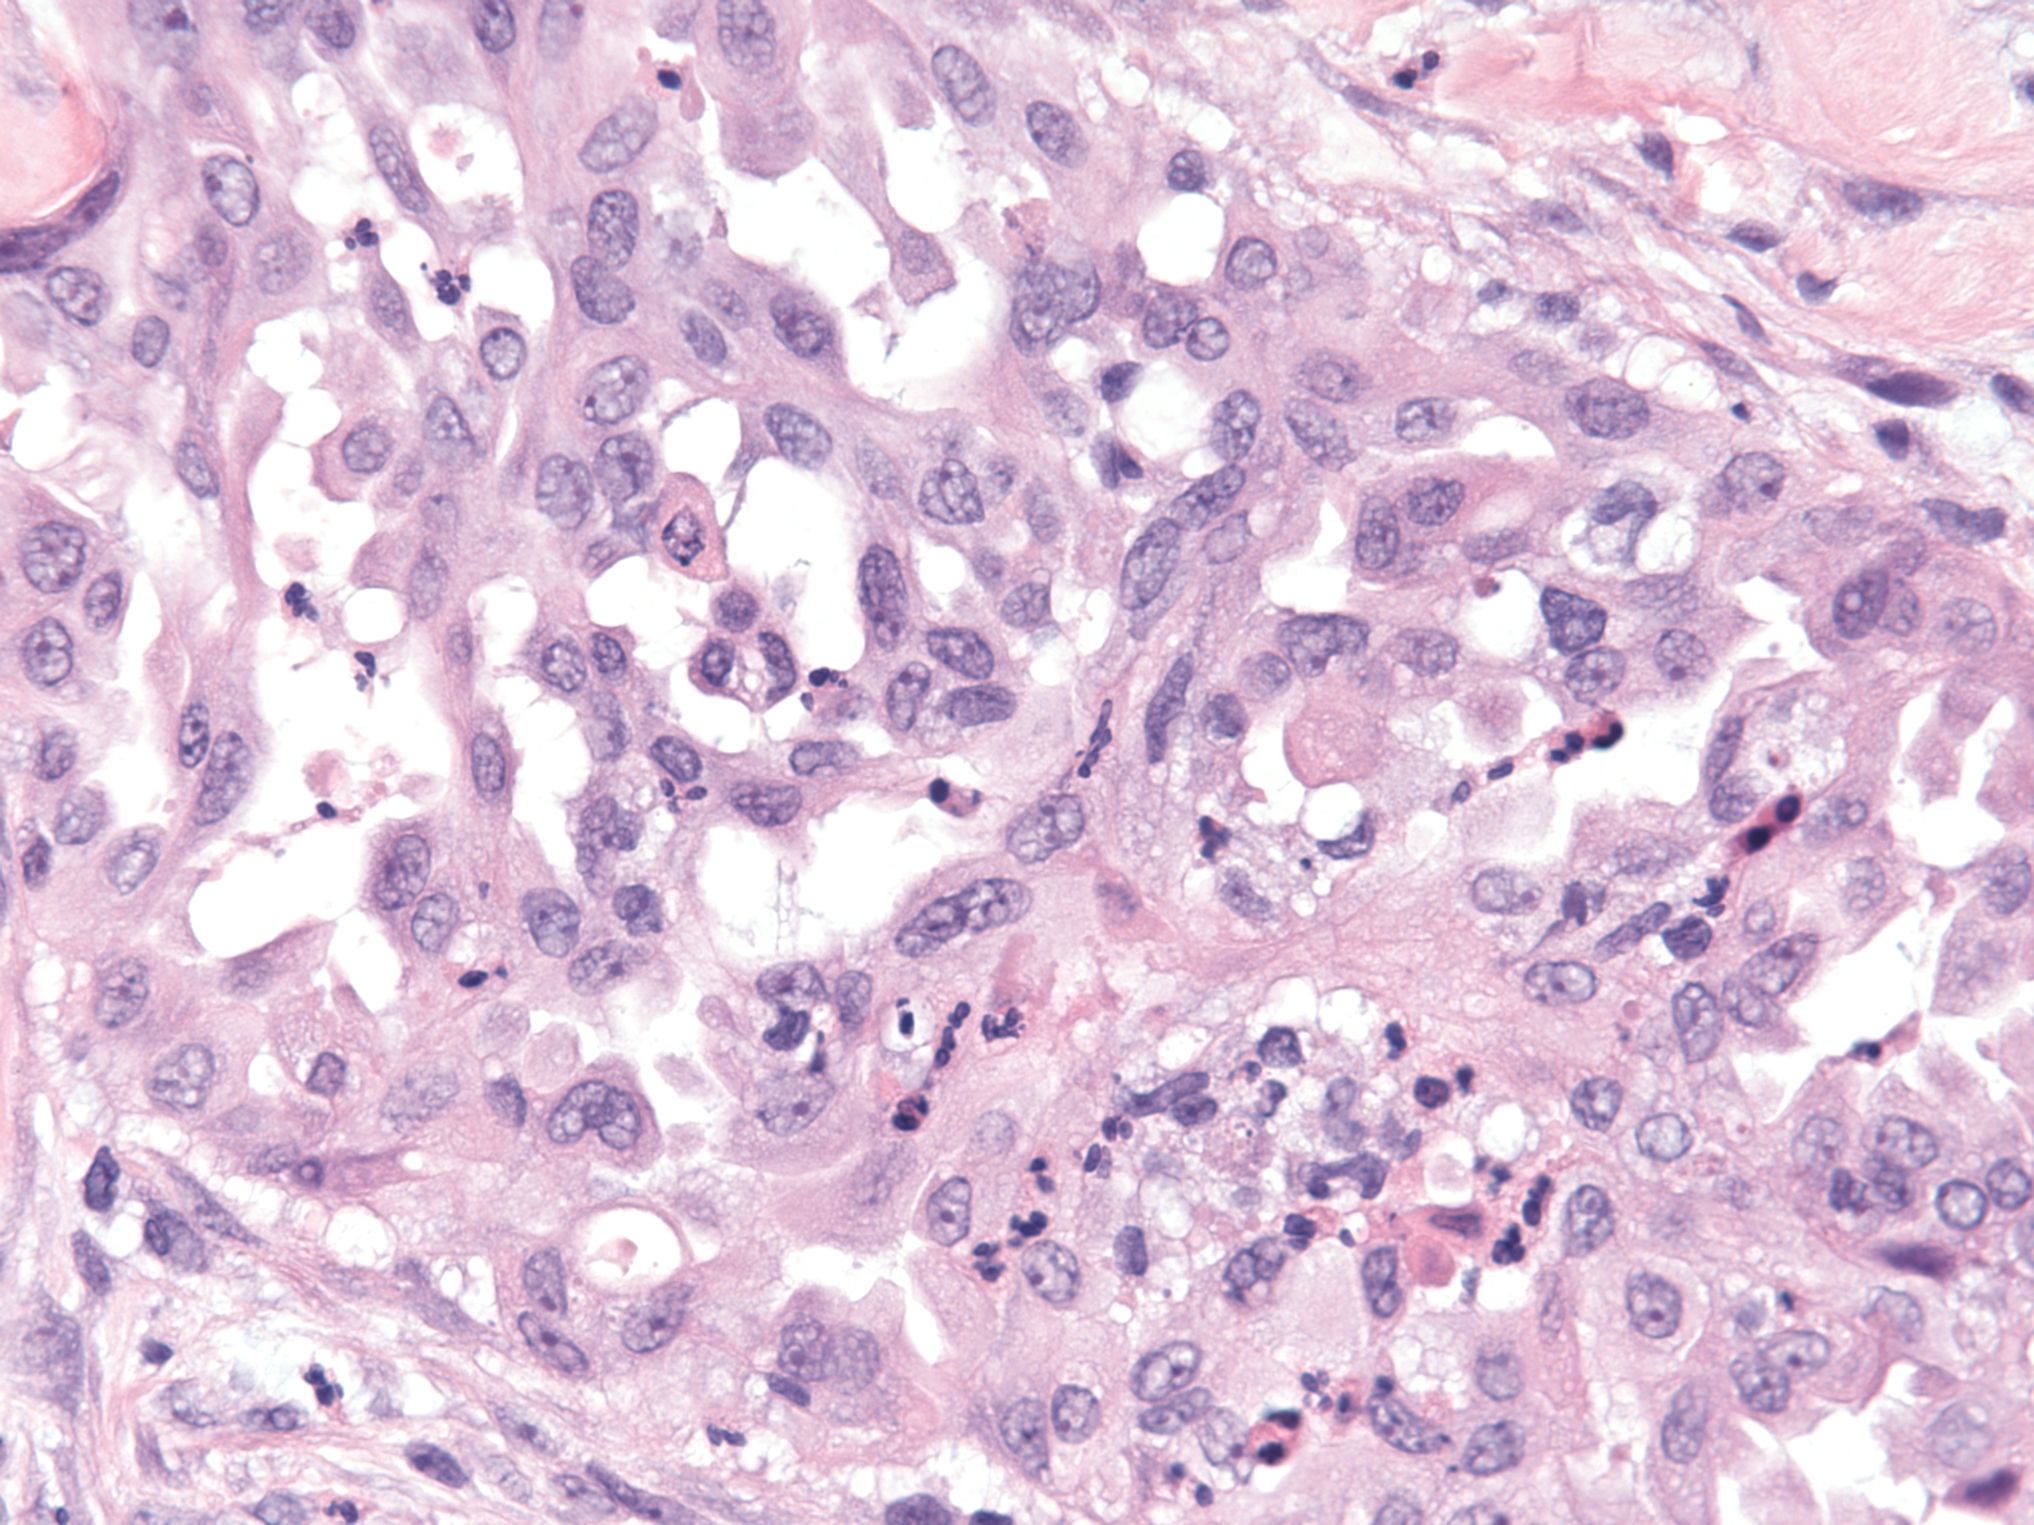

Microscopic (histologic) description

- Uniform / homogeneous population of small cells with scant cytoplasm

- Mild to moderate nuclear atypia at most (grade 1 or 2)

- No nuclear pleomorphism (< 3x variation in size) (Hum Pathol 2005;36:1049)

- May have a conspicuous nucleolus

- Low mitotic index: < 12 mitotic figures per 10 high power fields

- Little to no necrosis

- Psammoma bodies are frequent

- 2 patterns, noninvasive and invasive:

- Noninvasive: nonhierarchical architecture with micropapillary or cribriform patterns with significant expansile growth

- Invasive (> 5 mm): micropapillary or complex papillae, compact cell nests, inverted macropapillae (with broad fibrovascular cores), cribriform, glandular or cystic, solid sheets with slit-like spaces and single cells

- Multiple different invasive patterns can exist within one tumor

Microscopic (histologic) images